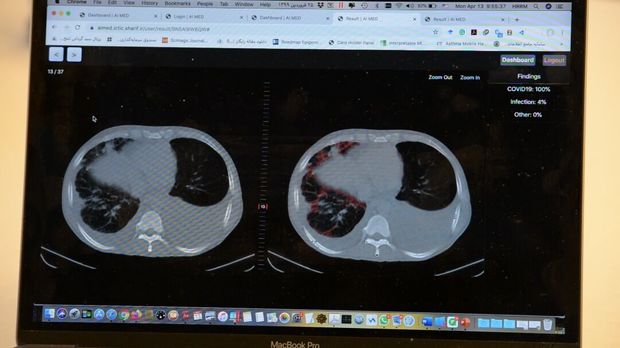

حمیدرضا ربیعی، استاد دانشگاه صنعتی شریف، عضو گروه علمی هوش مصنوعی در سلامت سازمان جهانی بهداشت (WHO) و رییس گروه علم و فناوری اطلاعات و ارتباطات جایزه مصطفی(ص) در خصوص سامانه هوشمند ایرانی تشخیص کووید ۱۹ با نام آی مد گفت: روش‌های مختلفی برای تشخیص کووید ۱۹ وجود دارد؛ اما یکی از بهترین روش‌ها که دقت بالایی دارد، استفاده از تصاویر سی‌تی اسکن قفسه سینه توسط پزشک متخصص است و تاکنون چندین فعالیت در راستای استفاده از هوش مصنوعی برای کمک به تشخیص این بیماری انجام شده است.

وی بیان کرد: کشور چین از هوش مصنوعی برای تشخیص این بیماری استفاده کرده است و یک شرکت برخاسته از دانشگاه استفورد آمریکا نیز فعالیت‌هایی را در این زمینه انجام داده است، ما نیز با تمرکز بر کاربرد هوش مصنوعی در سی تی اسکن، با نوآوری سامانه ای را برای تشخیص سریع و با دقت کووید ۱۹ طراحی کرده ایم که قابلیت تخمین حجم ناحیه عفونی را نیز دارد.

رییس گروه علم و فناوری اطلاعات و ارتباطات جایزه مصطفی(ص) همچنین افزود: سیستم‌هایی که در کشور چین یا آمریکا استفاده می‌شود، دقت بالای ۹۰ درصد دارند، نبوغ جوانان دانشمند ما، با پیش پردازش نوآورانه بر روی تصاویر سی‌تی اسکن و استفاده از راهکارهای توصیف پذیری در یادگیری ماشین، سامانه ای با دقت و حساسیت بالاتری را به وجود آورده است.

ربیعی گفت: سامانه ای که این تیم تحقیقاتی براساس هوش مصنوعی طراحی کرده است با نوآوری در پیش پردازش و پردازش تصاویر در شبکه‌های عمیق توصیف پذیر، به صورت پایدار و در زمانی کمتر از یک دقیقه، نتایج خوب و با دقت و حساسیت بالای ۹۷ درصد را به دست آورد. علاوه بر این سامانه حجم نواحی عفونی را نیز محاسبه می کند. این سامانه به طور رایگان در اختیار پزشکان و مراکز درمانی جهان قرار می‌گیرد تا با توجه به تعداد زیاد بیماران بتواند به پزشکان در تشخیص سریع و با دقت این بیماری کمک کند.

وی با بیان اینکه کوید ۱۹ در برخی از تصاویر در مراحل اولیه بیماری با چشم غیرقابل مشاهده است، اظهار کرد: از بیمارستان‌های مختلف، نمونه‌هایی را داشته‌ایم که امکان تشخیص این بیماری برای آن­ها از مشاهده تصاویر وجود نداشته است، اما سامانه هوشمند آی مد باتوجه به طراحی مناسب آن توانسته بیماری را در مراحل اولیه تشخیص دهد.